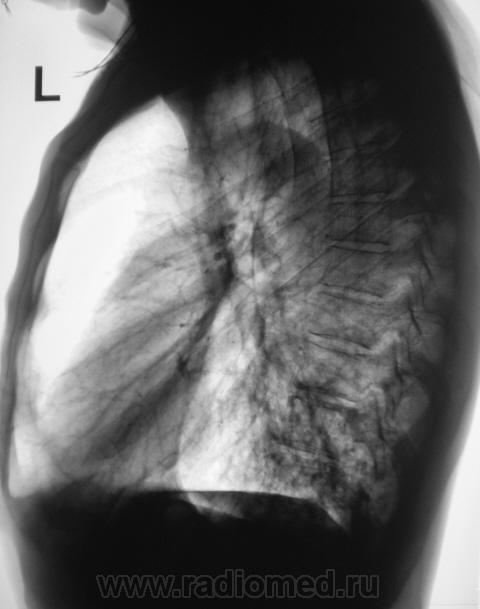

Пациент направлен на рентгенографию ОГК с диагнозом - "Левостороняя пневмония".

Анамнез стандартный. Ранее неоднократно страдал обострениями хронического бронхита. Сейчас вот не нашутку занемог - температура до 38, откашливает мокроту, кашель продуктивный.

Диагноз левосторонней нижнедолевой С10, С9 сементарной пневмонии наверное будет верным, а с учётом фона- с наличием бронхоэктазов.